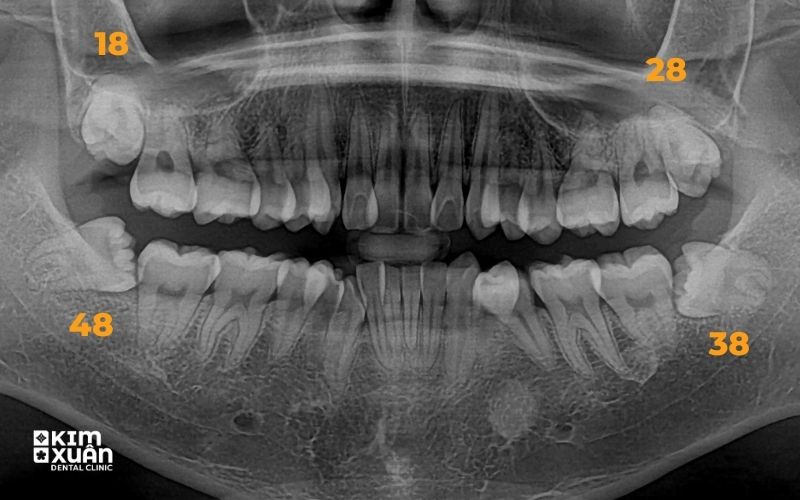

Không nên tự ý quyết định nhổ hay giữ răng số 8. Việc này cần được đánh giá dựa trên phim X-quang và thăm khám trực tiếp.

Để xác định chính xác chi phí nhổ răng khôn bị sâu, bác sĩ cần thăm khám trực tiếp và chụp phim X-quang nhằm đánh giá vị trí răng, mức độ sâu, tình trạng viêm nhiễm cũng như ảnh hưởng của răng số 8 đến các răng lân cận.

Chụp phim X-quang đánh giá chính xác vị trí và mức độ răng khôn